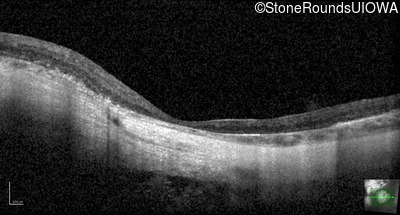

Optical Coherence Tomography - Left - 20/160 -2

Exemplar / OCT Stack

OCT Stack